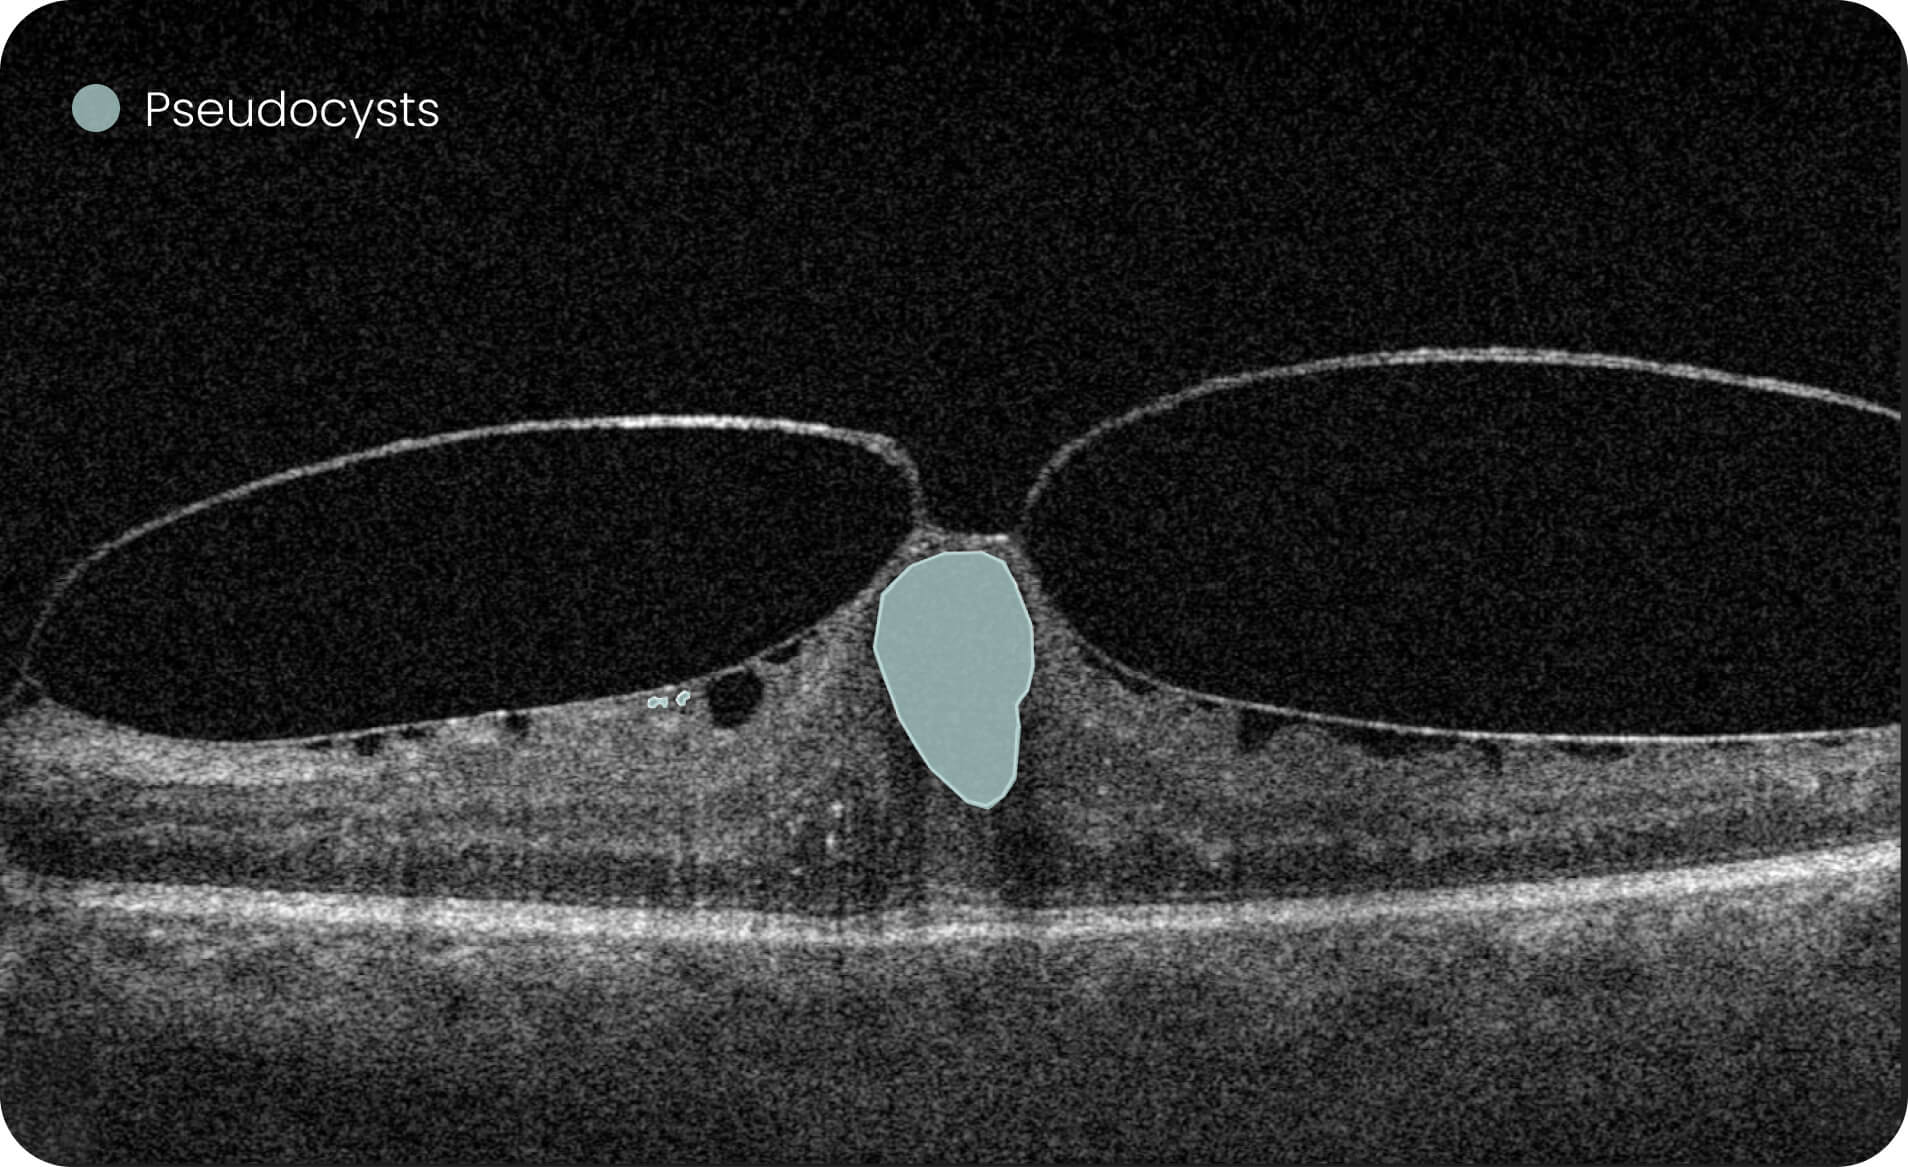

Characterization and visualization of OCT features commonly studied in Geographic Atrophy (GA), including hypertransmission, RPE atrophy, neurosensory retinal atrophy, and EZ changes.

Quantitative, image-derived measurements of GA-related features and associated biomarkers for research analyses.

- 40+retinal biomarkers studied in research across 30+ retinal conditions. For Research Use Only. Not for diagnostic procedures.

- Quantitative exploration of 40+ biomarkers for Research Use Only. Not for diagnostic procedures.